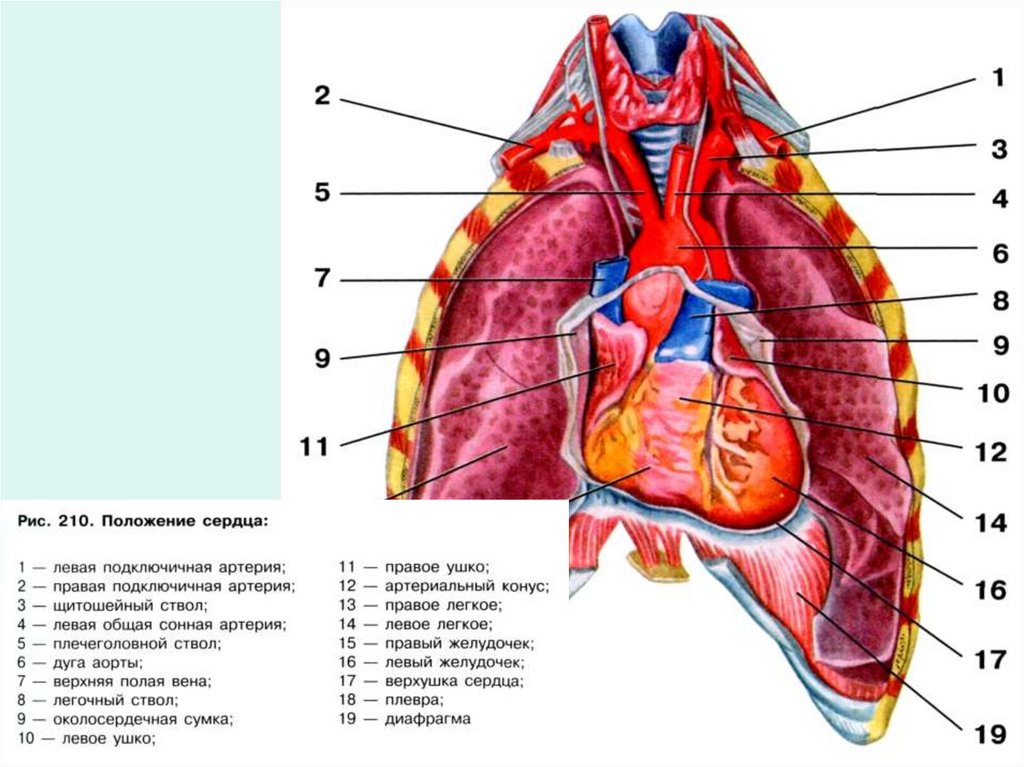

Анатомия Сердца: Расположение и Функции